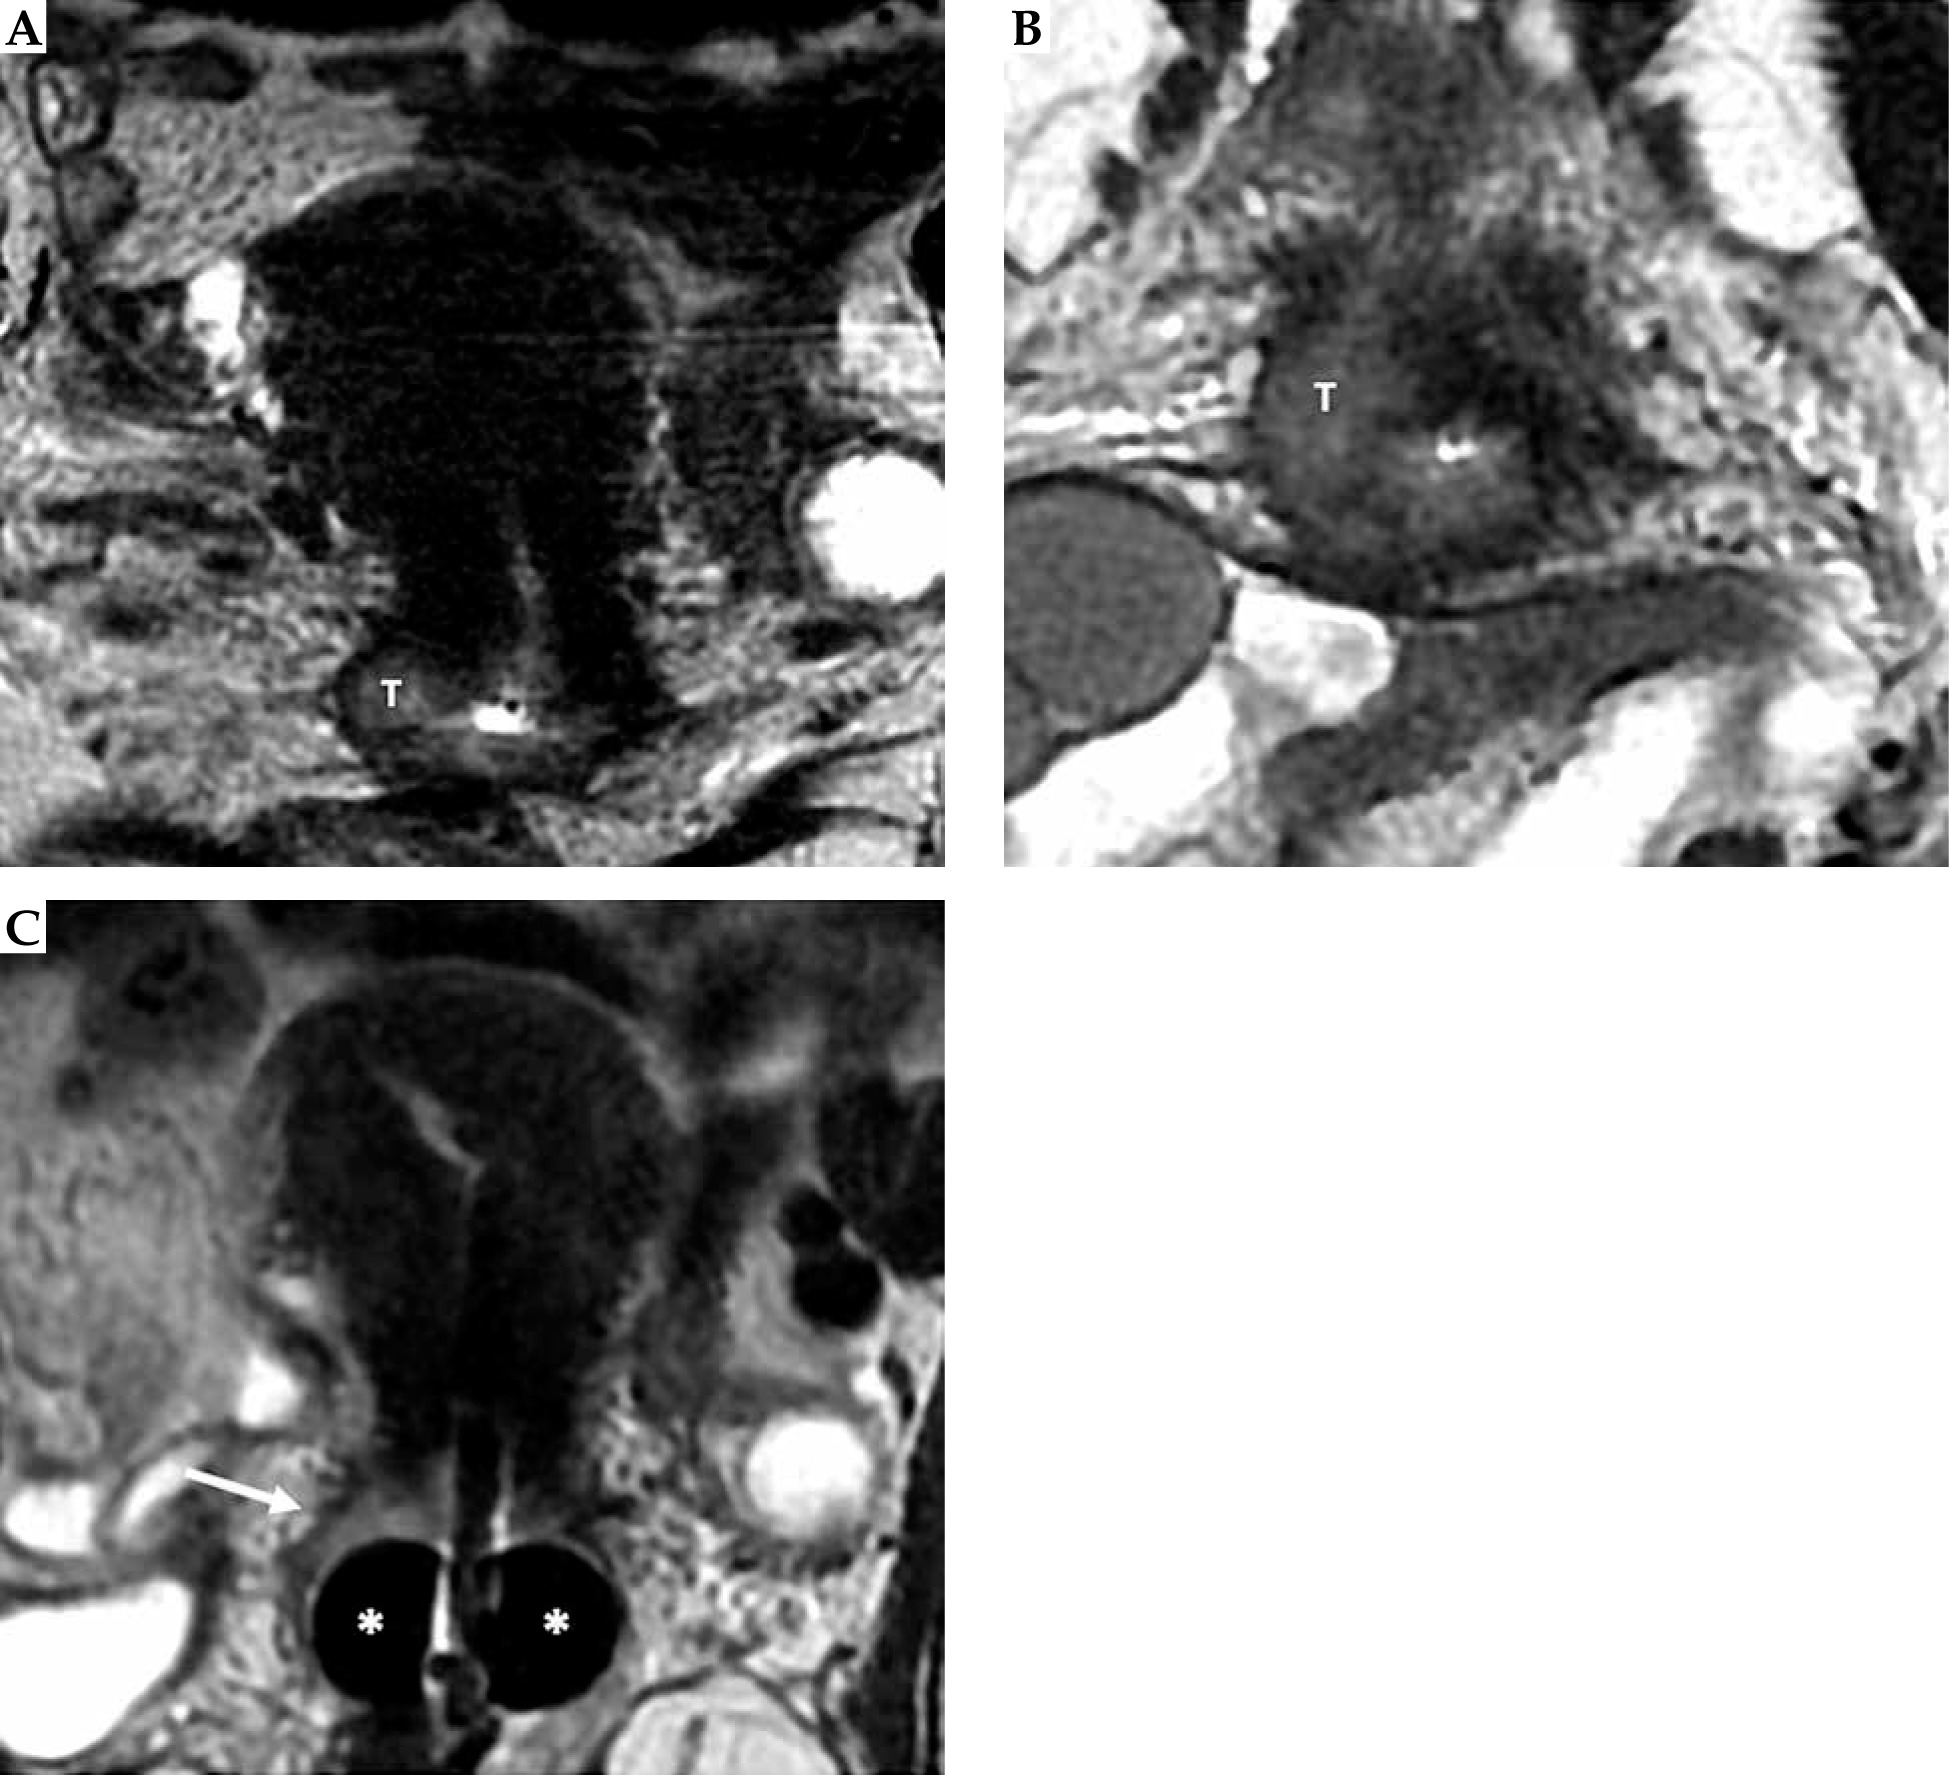

Fig. 4

Cervical cancer in a 55-year-old woman who underwent MR imaging with applicator. Sagittal (A), axial (B), and coronal (C) images, respectively, perpendicular and parallel to the plane of the applicator show tandem (arrow) in place. On axial plane (B), tumor (T) is located around the tandem from 7 to 1 o’clock (dotted line)

Fig. 10

34-year-woman with squamous cell cervical carcinoma. Post-external beam radiotherapy (EBRT) axial oblique T2-weighted image (A) indicates high signal-intensity residual tumor (T) extending in the right and posterior parametria. Post-applicator MRI (B-D) shows the relationship between the applicator and the residual tumor. In this case, interstitial needles (arrows in C) were placed to cover parametrial extension of the tumor